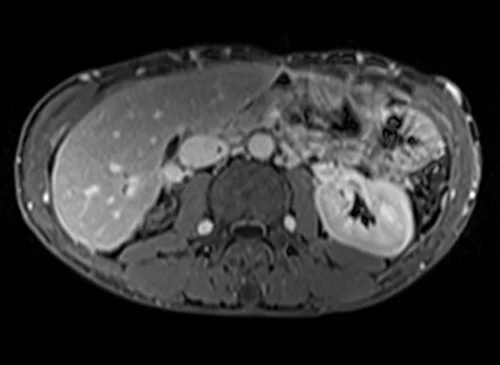

MRV abdomen axial t1 flash post contrast image 4 - MRI